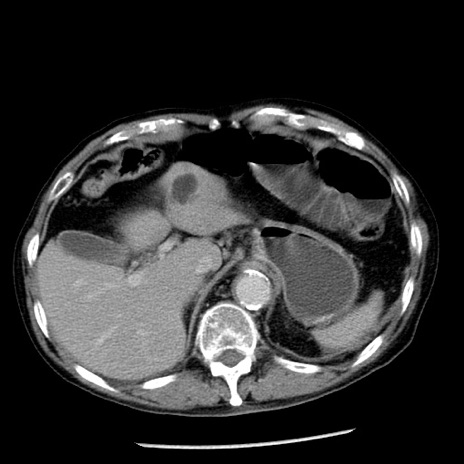

冠状断像

【症例】80歳代男性

【主訴】嘔吐

【現病歴】昨晩2回嘔吐あり、今朝になっても嘔吐あり。来院。

【既往歴】胃潰瘍

【身体所見】意識清明、BT 37.6℃、BP 166/95mmHg、HR 100bpm、SpO2 97%、腹部:平坦・軟、腸蠕動音聴取良好、圧痛なし。

【データ】WBC 21900、CRP 1.46